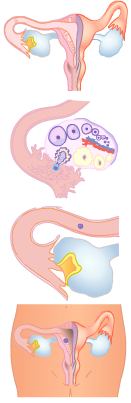

De weg van de eicel

Bij meisjes vanaf ongeveer elf jaar rijpt er in de eierstokken elke maand één eicel. Bij de eisprong ofwel ovulatie komt de eicel in de eitrechter, het begin van de eileiders. Een eventuele bevruchting vindt plaats in de eileider. De eileider sluit aan op de baarmoeder.

Bij meisjes vanaf ongeveer elf jaar rijpt er in de eierstokken elke maand één eicel. Bij de eisprong ofwel ovulatie komt de eicel in de eitrechter, het begin van de eileiders. Een eventuele bevruchting vindt plaats in de eileider. De eileider sluit aan op de baarmoeder.

De baarmoederwand bestaat uit spieren plus een slijmlaag: het baarmoederslijmvlies.

In de baarmoeder kan een bevruchte eicel ofwel zygote uitgroeien tot een baby. De baarmoeder is hol en loopt taps toe. Dat gedeelte heet de baarmoederhals. De holte staat met de baarmoeder in verbinding met de vagina (schede).

De vagina (schede) verbindt de baarmoeder met de buitenwereld. Daardoor gaat bij de geboorte het kind naar buiten.